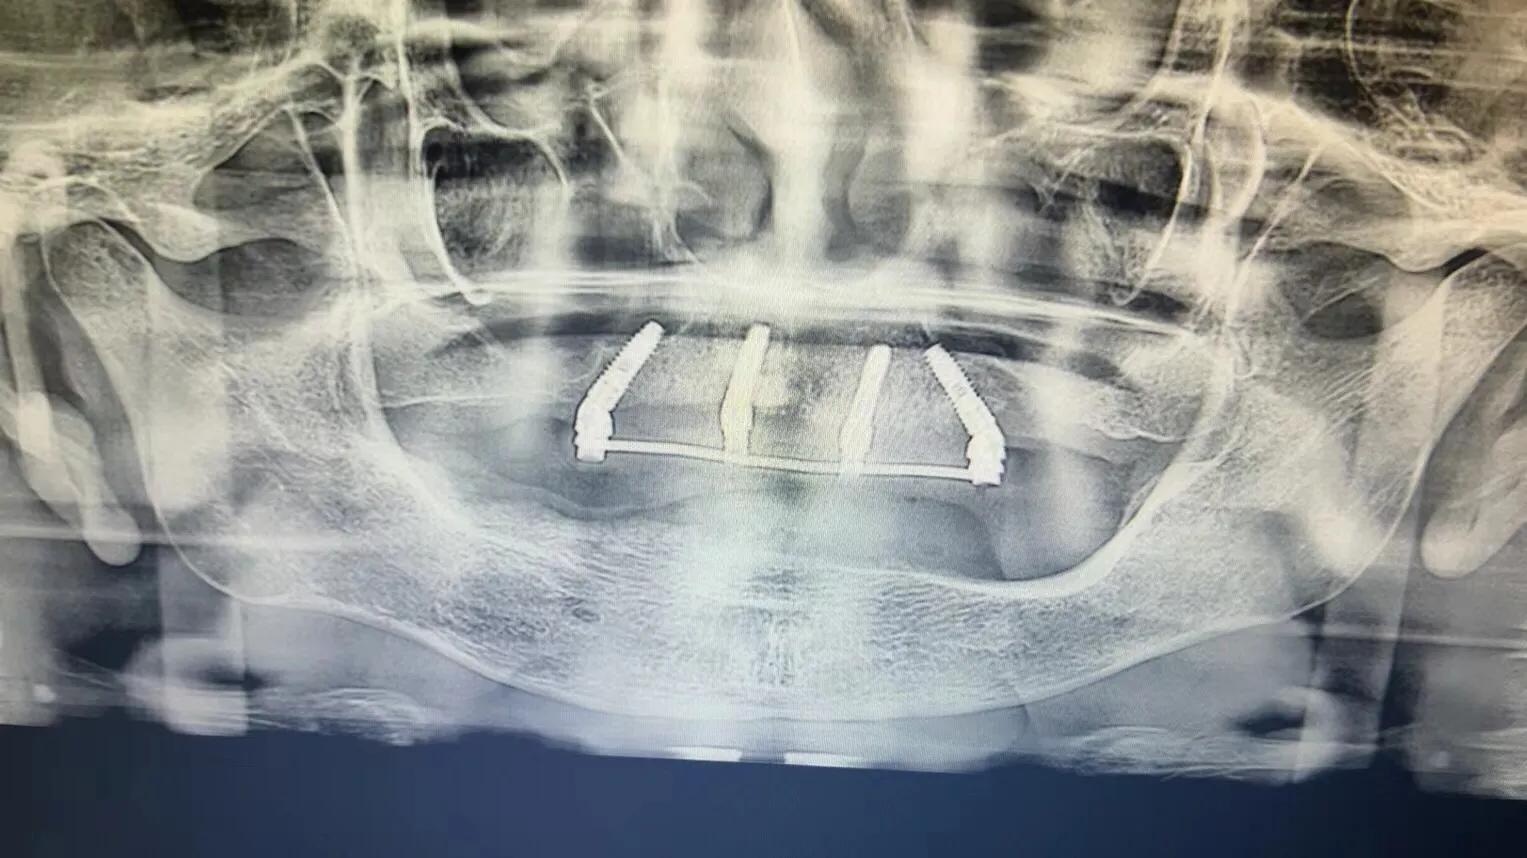

典型的負(fù)重,All-On-4。

這就是傳說中的當(dāng)天戴牙當(dāng)天吃飯,網(wǎng)上到處宣傳的就是這種種植方法。但是不是每一個(gè)人都能做這個(gè),All-on-4一般需要預(yù)約,醫(yī)生種植完畢,技師馬上開始取模做牙,大概5小時(shí)左右就可以戴上臨時(shí)牙回家吃飯了,休息一兩天,正常吃飯是沒問題的。

2. 還有一個(gè)問題就是骨件,不是每個(gè)人都可以做。骨頭太差,只能做常規(guī)的種植,等3-6個(gè)月戴牙,可能更久,中間只能用臨時(shí)牙過度。負(fù)重開始戴的也是臨時(shí)牙,但是這個(gè)臨時(shí)牙和常規(guī)島臨時(shí)牙不一樣,咬合力挺好